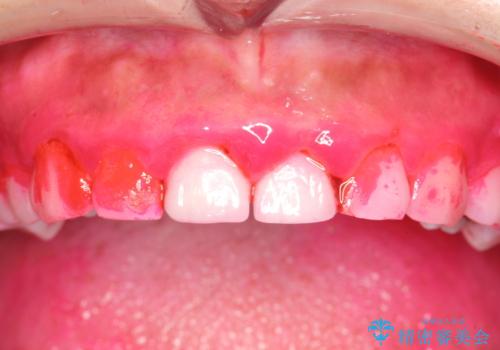

ナイトガードを作成前にPMTCできれいに

- 夜間の歯ぎしり・食いしばり予防のナイトガードを作成希望とのことで来院されました。しばらくクリーニングも受けていないとのことでPMTC30分コースを行いました。

プラークや歯石により、歯肉が炎症している場合、歯と歯肉の境目が鮮明に型取り出来ないなどがあります。そのため、マウスピースの作成前などには、PMTCで歯の表面の汚れを落とすことで、仕上がりのマウスピースがより精密なものとなります。